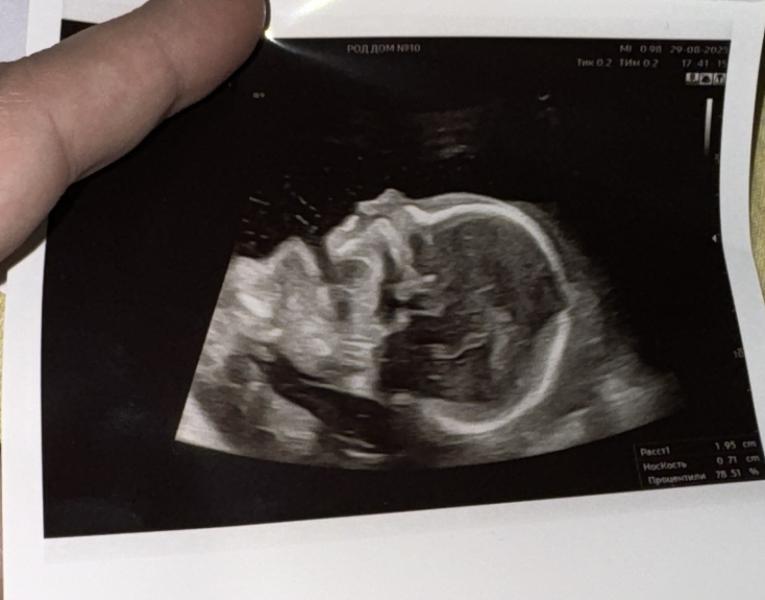

Спешу поделиться своей радостной новостью - после долгих попыток - я наконец-то жду малыша 🥰 🤰

Беременность не самая простая, поэтому раньше не решалась делиться этим (думаю, что позже напишу на эту тему)